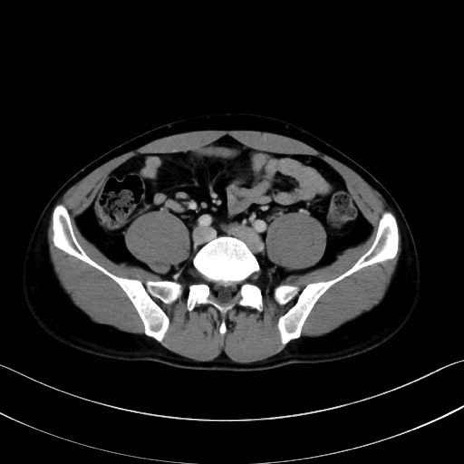

腰方形筋(quadratus lumborum muscle)のCT画像の解剖

腰方形筋 (Quadratus lumborum)

2. 腸腰筋群と骨盤底筋

大腰筋 (Psoas major)

腸骨筋 (Iliacus)